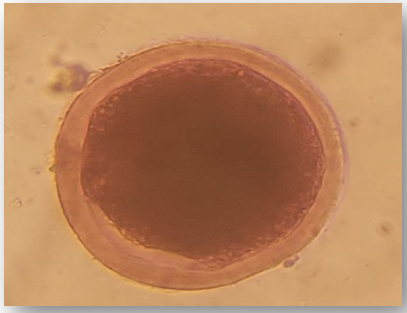

After were collection of oocytes, examine the viability for all oocytes after it has been prepared and washed in laboratory, with trypan blue to classified it into live (viable) oocytes (unstained)(figure 10 A), and dead (non-viable) oocytes (full stain)(figure 10B). To assess the oocytes viability and membrane integrity of the oocytes were used the trypan blue stain (vital dye). Trypan blue is a dye used to measure the viable (live) oocytes by tagging non-viable (dead) oocytes only(6).

Trypan blue cannot pass through cell membrane of the viable oocytes and penetrate cytoplasm, but in the non-viable oocytes, its inter the membrane through porous and penetrate the cytoplasm and color it blue. As a result, all blue oocytes were dead, while non-blue oocytes are viable [17].

Figure 10. Non-Viable Oocyte (dead) After Trypan Blue